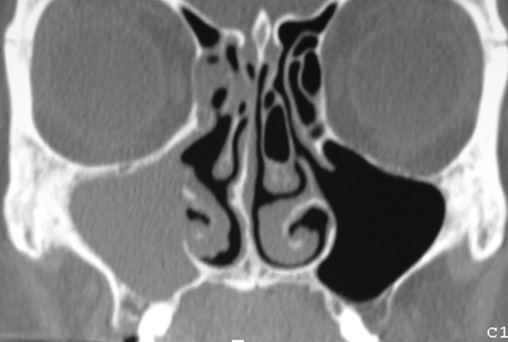

sinus max

Un bilan par une endoscopie lors d une consultation est essentiel en cas de récidive ou de persistance surtout apres un premier traitement tres souvent effectué par votre médecin traitant. Parfois, il est demandé un bilan complémentaire par un scanner des sinus ou des dents soit en urgence, soit à distance du traitement.

sinusite max  03